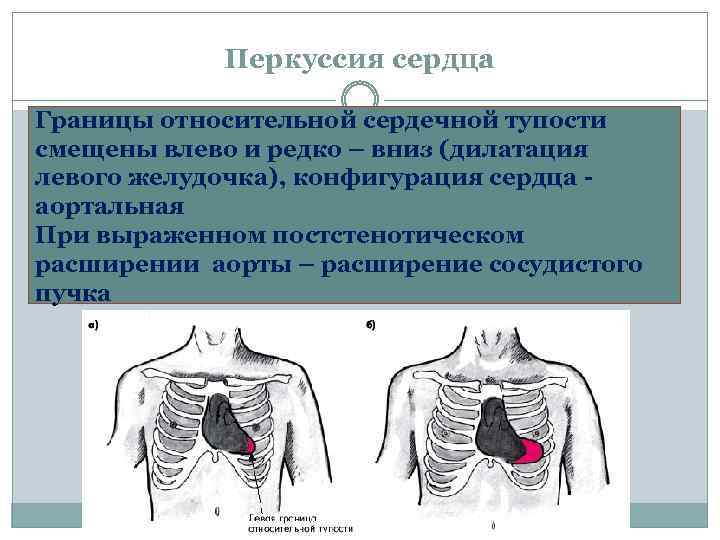

Перкуссия сердца Границы относительной сердечной тупости смещены влево и редко – вниз (дилатация левого желудочка), конфигурация сердца аортальная При выраженном постстенотическом расширении аорты – расширение сосудистого пучка